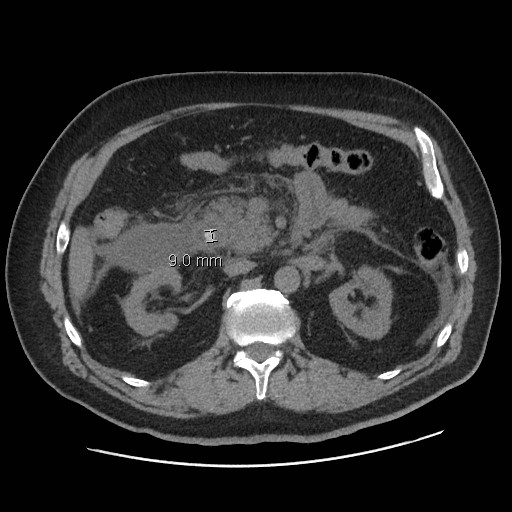

Ont été inclus tous les patients ayant consulté en urgence en Angleterre entre 2008 et 2010 et chez lesquels le diagnostic de pancréatite biliaire aiguë (PBA) avait été affirmé sur des arguments cliniques, biologiques et radiologiques en ne retenant pas ceux qui avaient un antécédent de PBA dans l’année ou qui avaient déjà subi cholécystectomie ou SE. Les malades décédés avant traitement et suivis en unités de soins intensifs (USI) ont également été exclus.

Le TPD était défini comme l’exécution de la cholécystectomie ou de la SE au cours de l’hospitalisation ou dans les 15 j suivants. Il a été tenu compte des facteurs de gravité que sont l’âge, les pathologies associées, le statut socio-économique et la spécialisation des hôpitaux où les soins étaient prodigués.Sur près de 22 000 PBA recensées, plus de 10 % ont été exclues (épisode de PBA dans l’année, décès ou passage en USI), laissant 19 510 sujets, dont seulement 6 733 (4 245 femmes) avaient bénéficié du TPD, soit 34,5 %. Ces 6 733 cas se décomposent en 5 553 ayant eu un TPD lors de l’hospitalisation (2 168 cholécystectomies, 3 111 SE, et 274 couplant les deux), et 1 180 traités dans les 15 j (794 cholécystectomies, 386 SE). Au terme d’un an, ils étaient 14 474 à avoir reçu un traitement définitif (TD), et 5 036 (26 %) à ne l’avoir pas reçu, cette proportion variant considérablement (de 15 à 90 %) selon les hôpitaux.